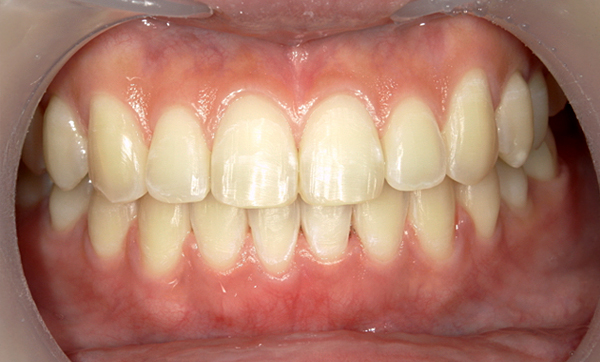

症例_009 「上下の前歯」症例

治療期間:7ヶ月金額:54万円+税20代女性捻転歯一部の反対咬合前歯のガタガタ